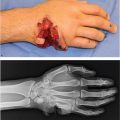

Complete, likely simple, syndactyly involving right long and ring fingers.

Complete syndactyly: Fusion involves entire length of the finger to distal tip, including nail fold.